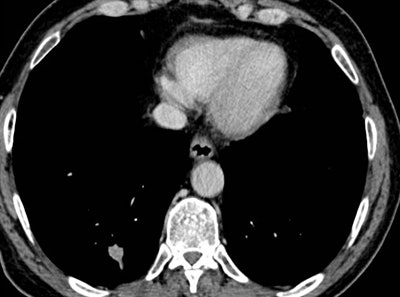

In her Liverpool talk, Strickland showed examples of missed lung cancers. In one case, leading to a duty of candour procedure, the lung bases, visible on a CT scan of the abdomen performed for suspected pancreatic pathology, had not been looked at on lung contrast windows, causing a small right basal lung cancer to be missed (see images above). On a subsequent chest CT scan several months later, the lesion was much bigger, and a second cancer was present in the left upper lobe. A duty of candour was issued because the lung cancer was at a higher stage when it was finally detected, likely leading to a worse outcome for the patient.

As we discussed in consultation this morning, I am very sorry that your CT scan undertaken to investigate pain in your abdomen and pancreas on Xth April 2014 did, in fact, show a small nodule in the bottom of the right lung. It is likely this was the early stage of the squamous cell cancer that we have now found in the right lung and are planning to treat.

A full and thorough investigation will be carried out by XXX Hospital as to why this small nodule was overlooked on the CT scan and why the scan was not flagged to the lung cancer team.